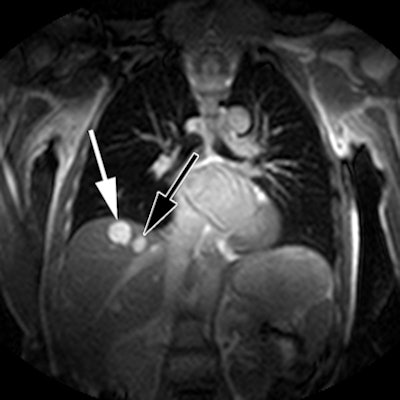

![]() |

| Benign liver lesions, cysts, or hemangiomas (arrows) are found in a 54-year-old man referred for assessment of hypertrophic obstructive cardiomyopathy after coronal SSPF MRI. All images courtesy of the American Journal of Roentgenology. |